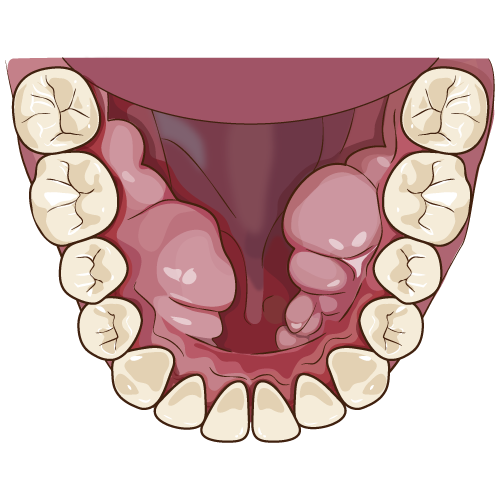

睡眠中に行う食いしばりは、起きているときの何倍もの力で噛んでいることが分かっています。毎晩、長時間にわたり上下の歯をこすり合わせていると、歯が削れてしまったり、歯が欠けたり、最悪の場合歯が折れてしまったりしてしまいます。歯が損傷されなくても歯を支えている歯根膜と呼ばれる感覚受容体が炎症を起こし歯の痛みとして感じることもあります。また、噛むことに使用する、咬筋とよばれる筋肉の炎症による痛みや、顎関節にかかる負担による顎関節症の誘発などもあります。人の組織は力がかかるところが発達してしまう傾向があります。いわゆる「えら」がはった顔貌の原因にもなってしまいます。口の中に下顎隆起とよばれる骨の塊ができてしまうこともあります。